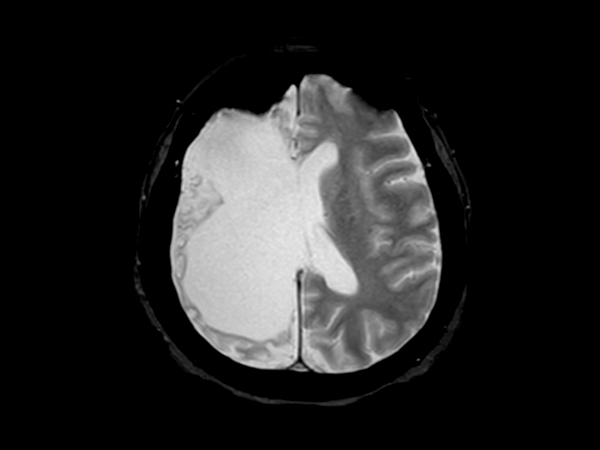

Axial T2w TSE